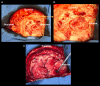

Intraoperative magnetic resonance imaging (iMRI) is a powerful tool used to verify maximal safe resection of gliomas. However, unsuspected new or incidental findings can present difficult clinical scenarios. Here we present a case of a large supratentorial glioma resection where new, incidental bilateral cerebellar hemispheric enhancement was noted on iMRI. A 52-year-old male with a large intra-axial mass spanning the right temporal and parietal lobes underwent a craniotomy for tumor resection utilizing iMRI. Imaging displayed new, remote, bilateral cerebellar enhancement. Upon completion of surgery, the patient was extubated and was at his neurological baseline. An immediate CT scan showed no abnormalities in the cerebellum, and the duration of his hospital stay was unaffected by this finding. An MRI 24 hours after the procedure demonstrated complete resolution of the enhancement. New, remote contrast enhancement in the cerebellum raises concerns for the potentially emergent, well-defined pathology known as remote cerebellar hemorrhage (RCH). However, here we describe a case where these findings turned out to be clinically insignificant, CT-negative, and self-limiting. Therefore, here we call this finding remote non-hemorrhagic cerebellar contrast enhancement (RNHCCE) to differentiate it from RCE, and we discuss nuances and management considerations for differentiating the two.